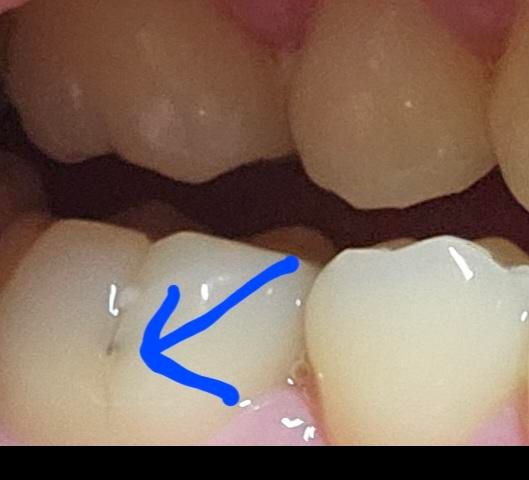

어금니 옆면에 검은색줄이 생겻는데 이거 충치 맞는거죠? 단음식 먹고나면 치통이 잇습니다 이정도면 충치범위?가 어느정도 진행되엇는지와 무슨치료를 받아야 되는지 궁금합니다

충치 맞습니다. 그러나 충치가 깊지 않아 충치제거하고 바로 떼우는 치료 가능할 것으로 보입니다.

사진상으로 보면 충치가 조금 잇는거 같습니다. 정확한건 치과에 가셔서 엑스레이를 먼저 찍어보시고 치료를 하시는게 좋을것같습니다.

충치는 맞는 것으로 보이며 충치의 범위나 치료 계획 등은 여러가지 검사를 해본 후에 알 수 있습니다.

buccal pit 부위이고요. 충치 내지는 변색 같습니다. 충치가 커보이진 않으나 치통 증상이 있으므로 치과 가서 엑스레이 찍어보면 좋을 것 같습니다. 충치 제거하고 치과 재료로 떼우는 치료를 받게 됩니다.

사진으로 봤을 경우에는 초기 충치가 맞는것으로 보입니다. 충치인경우 치료가 필요할수 있으니 치과에서 진료를 받아 보는것이 좋습니다.